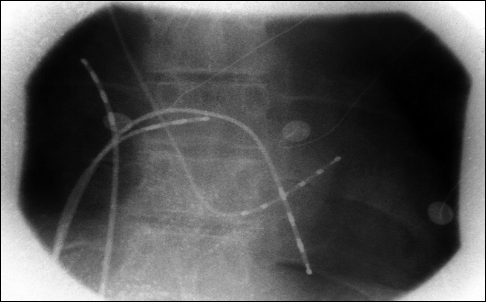

2. 导管置入:将数根细长、柔软的特制导管(消融导管和标测导管)通过血管通道,在X光透视或三维标测系统的引导下,送至心脏内部。

3. 心脏建模与标测:利用先进的三维电生理标测系统,在电脑上重建出患者心房的精确三维模型,并找出异常电活动的关键位置。

4. 消融:医生操控消融导管到达目标位置(如肺静脉口),通过释放能量来摧毁目标组织。主流的消融能量有三种: